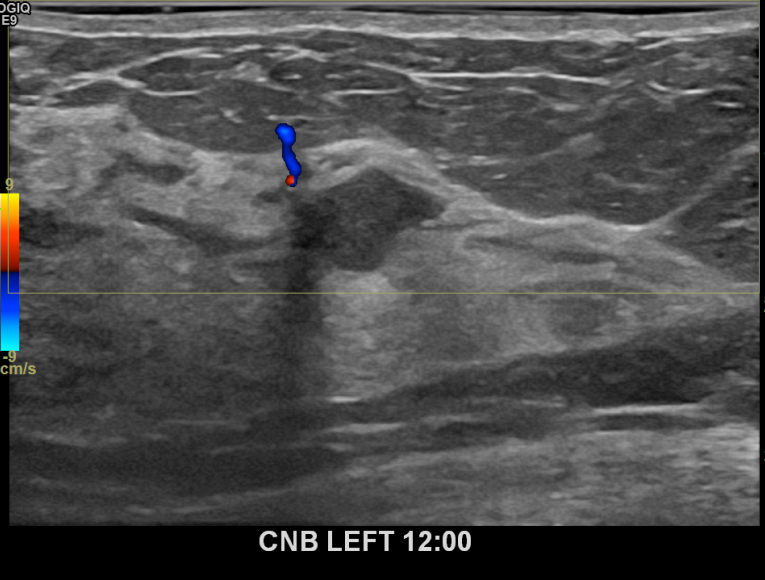

상기환자 좌측 유방통증 있어 내원하신 50대 여성분으로 좌측유방멍울 조직검사시행후 유방암 진단되었습니다.